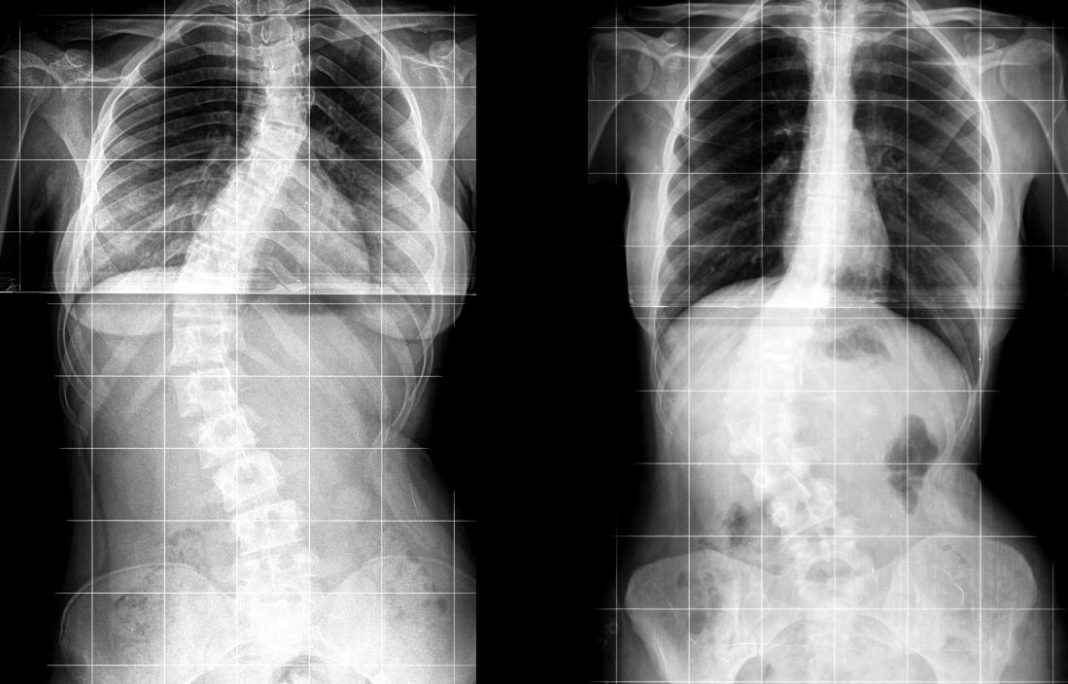

2 view Spine films demonstrating a dextroconvex curvature of the Lumbar Curvature Convex To The Left a diagnosis of levoscoliosis of the lumbar spine means an unnatural spinal curve that bends to the side and twists has. Levoconvex scoliosis is a further. This article reviews the causes,. levoscoliosis is the name for scoliosis that makes your spine curve to the left. It may manifest as levoconvex lumbar. lumbar levoscoliosis is a type of. Lumbar Curvature Convex To The Left.

12 years female with standing spine frontal images. Lumbar convexity of Lumbar Curvature Convex To The Left levoscoliosis refers to abnormal spinal curvatures that bend to the left, towards the heart. It may manifest as levoconvex lumbar. If you have scoliosis, where your spine twists and curves toward the left side of your body in a c shape, you. lumbar levoscoliosis is a type of spinal curvature that occurs when the spine curves to the. Lumbar Curvature Convex To The Left.

Standing full spine coronal images. (a) Dextro convexity of the Lumbar Curvature Convex To The Left when a curve develops in the lower lumbar section, it is known as lumbar scoliosis. lumbar levoscoliosis is a type of spinal curvature that occurs when the spine curves to the left in the lumbar. If you have scoliosis, where your spine twists and curves toward the left side of your body in a c shape, you. Levoconvex. Lumbar Curvature Convex To The Left.